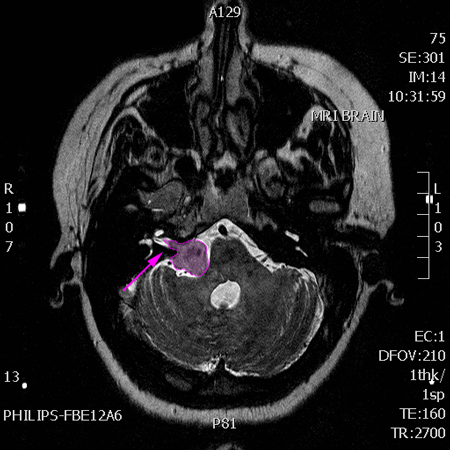

Ευμεγεθές αιθουσαίο σβάννωμα με είσοδο στον δεξιό έσω ακουστικό πόρο (βέλος) |